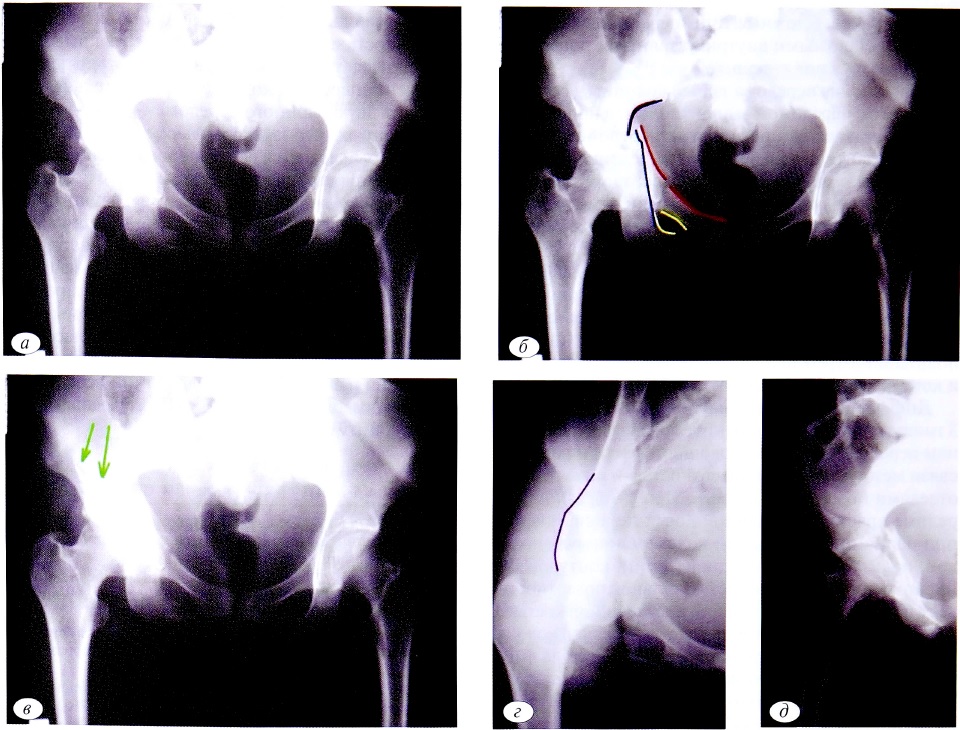

На рентгенограмме в прямой проекции (рис. 3, а) определяется нарушение целостности как подвздошно-гребешковой, так и подвздошно-седалищной линии в сочетании с нарушением целостности контуров запирательного отверстия и пространственной ориентации лобково-седалищного сегмента по сравнению с неповрежденной стороной.

На первом этапе диагностики исключаются все простые типы переломов: задней стенки, передней стенки, задней колонны, передней колонны, поперечного перелома. Также сочетание повреждений 3 линий позволяет исключить 2 типа переломов из группы ассоциированных: задней колонны, ассоциированный с переломом задней стенки, и поперечный, ассоциированный с переломом задней стенки, поскольку при этих типах переломов хотя бы одна из линий остается интактной (см. рис. 3, б).

Таким образом, можно сделать заключение, что сочетание повреждения подвздошно-гребешковой, подвздошно-седалищной линий и контуров запирательного отверстия характерно для Т-образного перелома, перелома передней колонны, ассоциированного с задним полупоперечным переломом, двухколонного перелома.

Сохранение целостности контуров крыла подвздошной кости позволяет исключить переломы с наличием отдельного фрагмента передней колонны: передней колонны, ассоциированный с задним полупоперечным, и двухколонный (см. рис. 3, в). Методом исключения был диагностирован Т-образный перелом вертлужной впадины.

Полипроекционные рентгенограммы подтвердили правильность установленного диагноза (см. рис. 3, г, д). Как в запирательной, так и в подвздошной проекции линия перелома проходит через обе колонны вертлужной впадины в одной плоскости по касательной к ее своду (юкстатектальный перелом).

Рис. 3. Пациент №3. а — обзорная рентгенография таза при поступлении; б — первый этап определения перелома; в — окончательное определение Т-образного перелома; г, д — верификация Т-образного перелома с помощью прицельных рентгенограмм.

Fig. 3. Patient №3. а — observational X-rays of the pelvis at admission; б — the first stage of fracture detection; в — final definition of a T-shaped fracture; г, д— verification of T-shaped fracture with sighting X-rays.

Наблюдение №4

В клиническом наблюдении на обзорной рентгенограмме таза также определяется повреждение 3 линий (подвздошно-гребешковая, подвздошно-седалищная линии, контуры запирательного отверстия), которое характерно для повреждения обеих колонн вертлужной впадины (рис. 4, а). Это позволяет на первом этапе исключить все простые типы переломов, а также 2 типа ассоциированных переломов: задней колонны, ассоциированного с переломом задней стенки, а также поперечного, ассоциированного с переломом задней стенки (см. рис. 4, б).

При дальнейшем анализе обзорной рентгенограммы можно выявить дополнительную плоскость перелома, проходящую через крыло подвздошной кости (см. рис. 4, в). Эта рентгенологическая особенность свидетельствует о наличии фрагмента передней колонны. При Т-образном переломе такой фрагмент отсутствует и, следовательно, этот тип повреждения также исключается.

Для дифференциальной диагностики оставшихся 2 типов переломов необходимо выполнение прицельной рентгенографии в запирательной проекции. В этом клиническом примере (рис. 4, г) определяется положительный симптом шпоры. Рентгенологически этот симптом обусловлен выведением контура заднего отдела подвздошной кости, который не имеет связи с суставной поверхностью (стрелка на рентгенограмме). Таким образом, методом исключения диагностирован двухколонный перелом вертлужной впадины.

Рентгенограмма в подвздошной проекции в случае двухколонного перелома позволяет подтвердить факт повреждения обеих колонн вертлужной впадины, но не дает возможность провести дифференциальную диагностику между двухколонным переломом и переломом передней колонны, ассоциированным с задним полупоперечным переломом (см. рис. 4, д).

Рис. 4. Пациент №4. а — обзорная рентгенография таза при поступлении; б — первый этап определения перелома; в — второй этап диагностики перелома; г — верификация двухколонного перелома (стрелками указан симптом шпоры); д — рентгенограмма в подвздошной проекции при двухколонном переломе.

Fig. 4. Patient №4. а — observational X-rays of the pelvis at admission; б — the first stage of fracture detection; в — the second stage of fracture diagnosis; г — verification of a two-column fracture (arrows indicate a symptom of spurs); д — X-ray in the iliac projection at a two-column fracture.